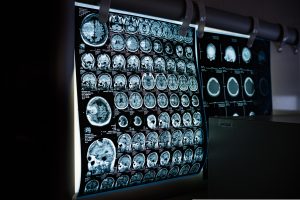

Snimak mozgaIstraživački tim sa Univerziteta Kembridž je analizirao 3.802 MRT snimka mozga i rekonstruisao obrasce neuronske povezanosti između rođenja i 90. godine. Podaci su otkrili iznenađujuće jasnu sliku: strukturna organizacija mozga ne odvija se kontinuirano, već u pet glavnih faza od kojih je svaka obeležena značajnim prekretnicama – oko 9. 32. 66. i 83. godine, piše […]